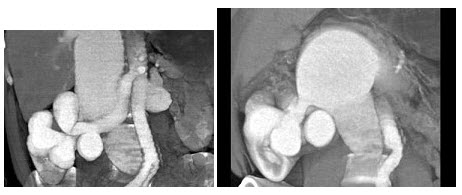

根据所提供的图像,推断此三维图像的数据是静脉注射后几秒采集的()

A.30s

B.60s

C.90s

D.180s

E.210s